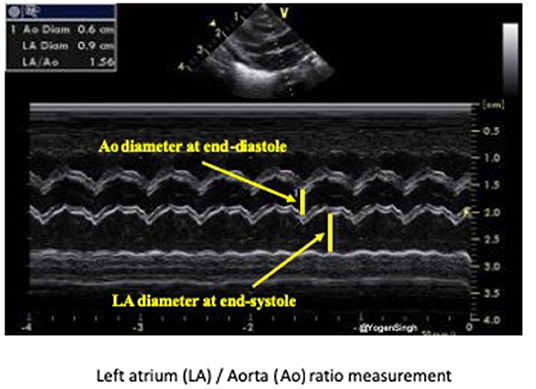

Both LA/Ao ratio and LVEDD can be measured from the parasternal long axis view using M-mode with the cursor perpendicular to the aorta at the level of the aortic valve or at the septum at the tip of the mitral valve leaflets, respectively (Figure 7). LA/Ao ratio of >1.4 is considered significant and has been used as a cut-off value in many clinical trials (25). The normal reference ranges for LVEDD in preterm infants in relation to body weight and postnatal age have been published and z-scores should be used for LVEDD (26).

Figure 7. Assessment of left atrium (LA) to aorta (Ao) ratio in parasternal long axis view. LA and Ao diameter measurement shown using M-mode and cartoon schematic diagram.